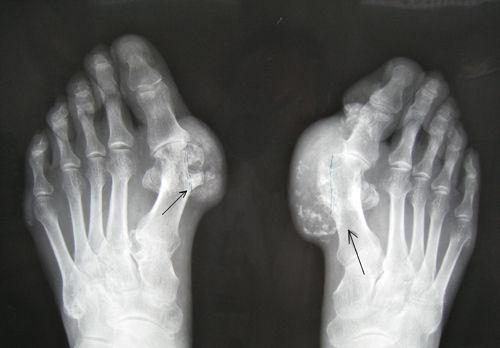

chopart骨折: 累及足的chopart关节的骨折脱位称为chopart骨折脱位